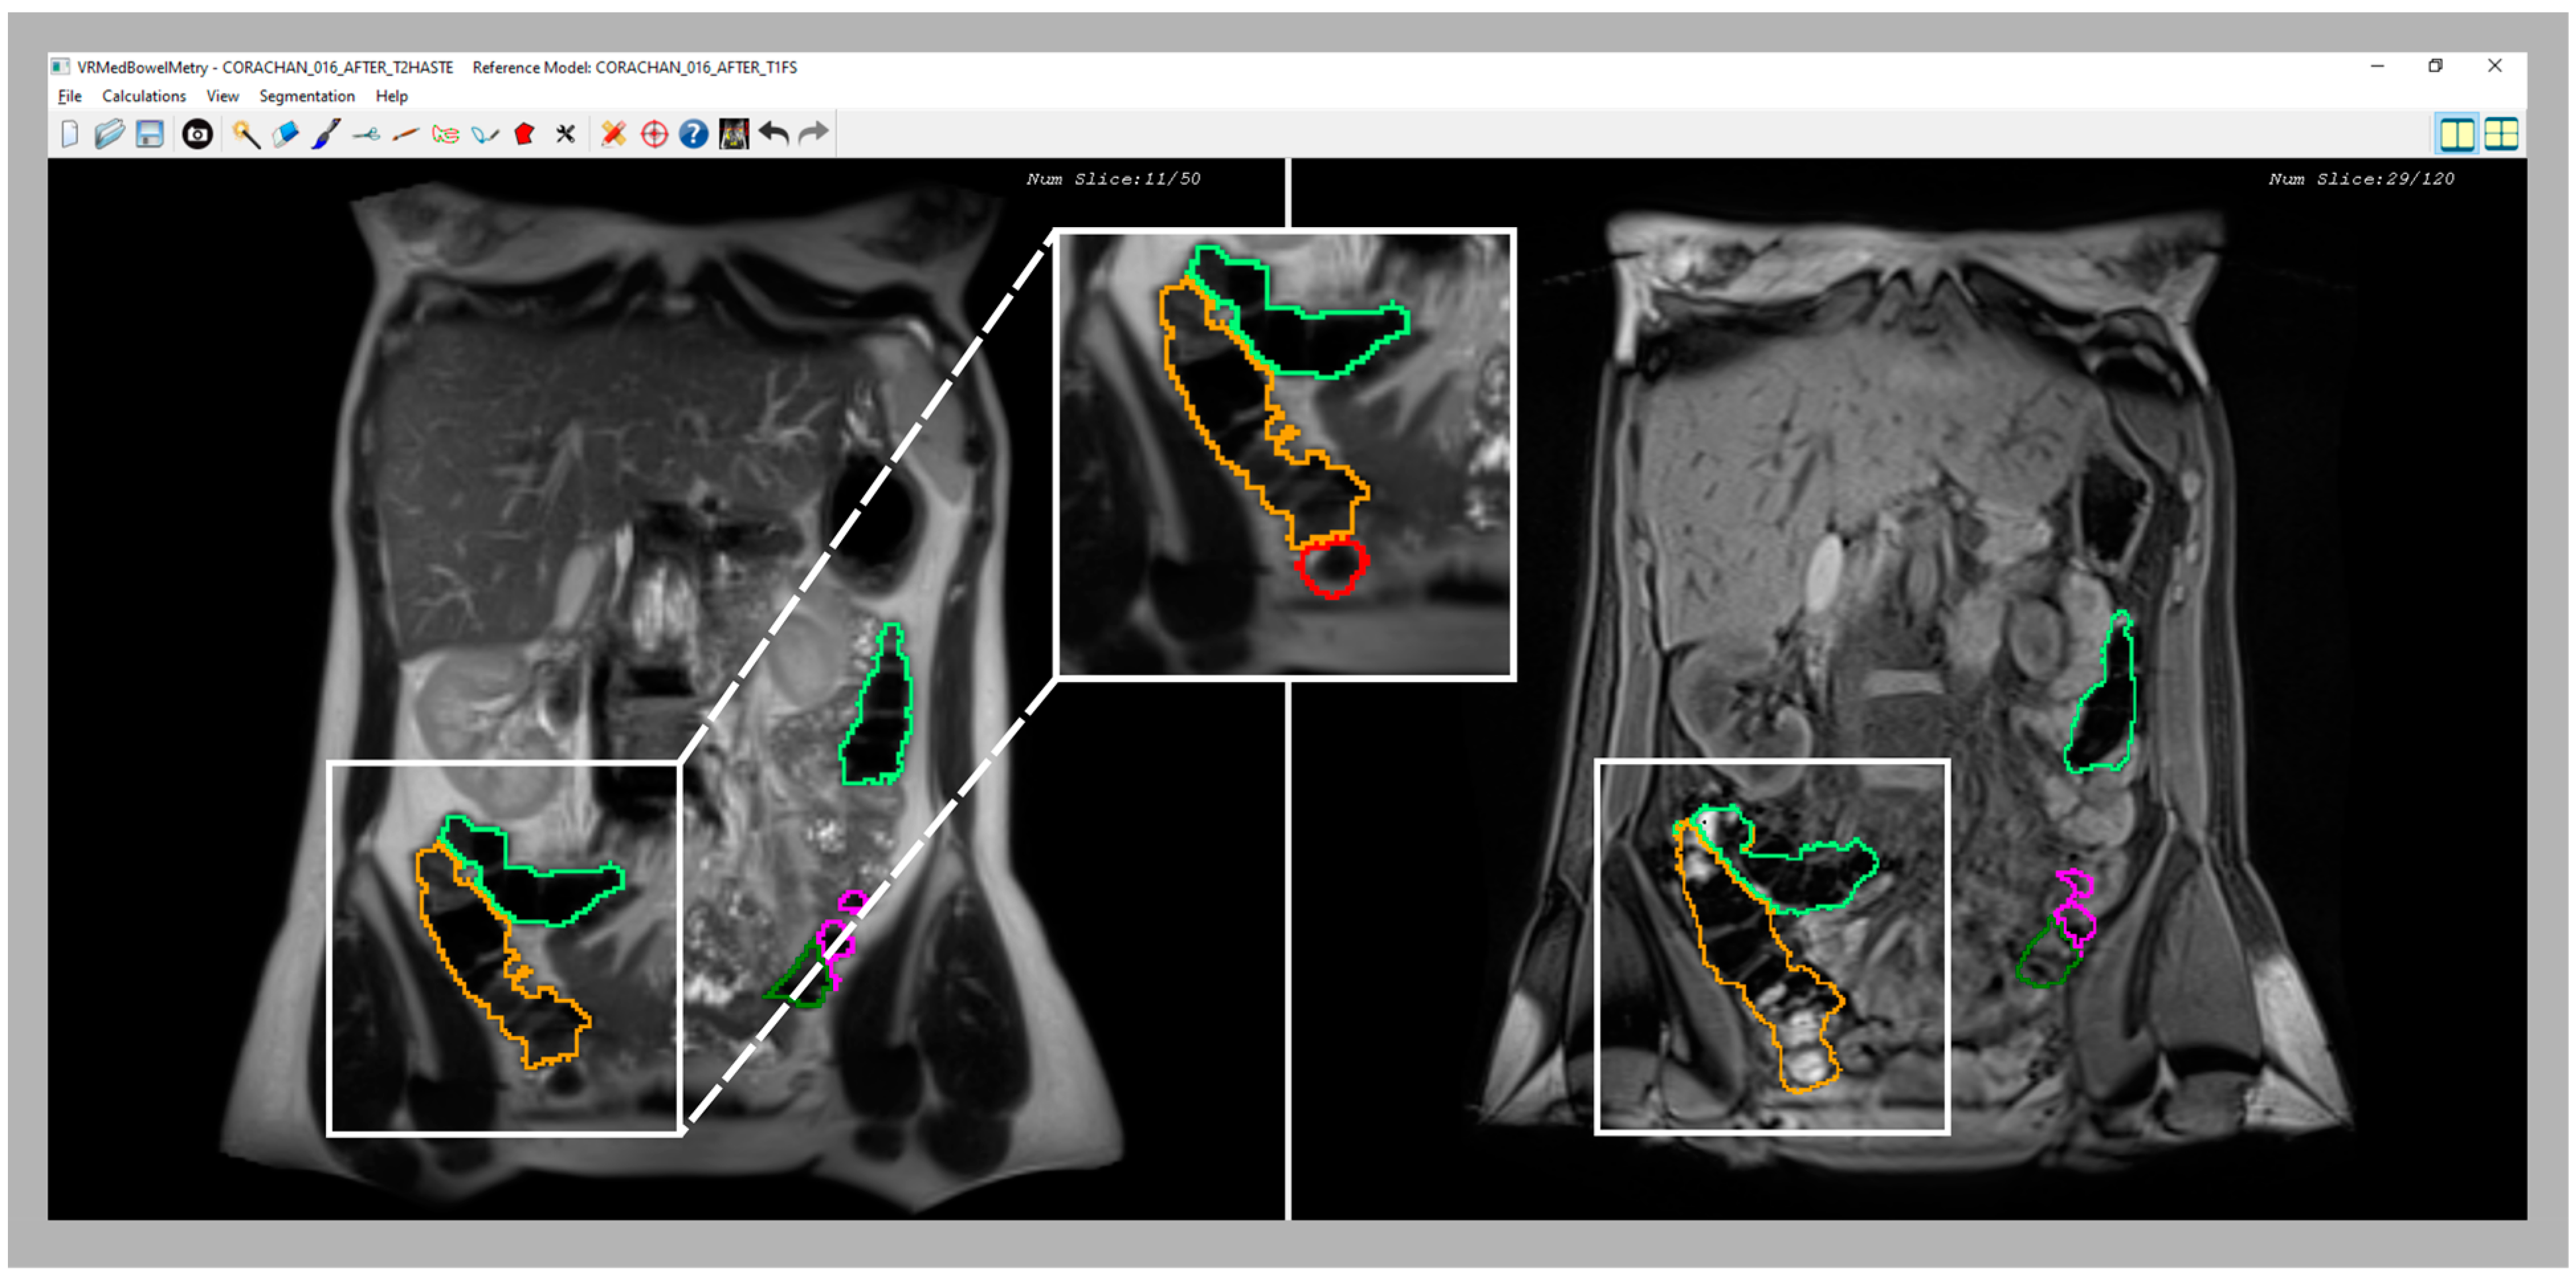

Figure 3 shows a snapshot of the application interface in which two T2 and T1-FS synchronized images of a segmented colon are visualized in two different windows. Every time the specialist clicks on a pixel of one image (T2 or T1-FS) the system automatically computes its corresponding pixel position in the other image (T1-FS or T2) by transforming the pixel position using the formula previously presented. Moreover, using the mouse wheel, the user can navigate forward and backward around the images in a synchronous fashion following the same scheme: when the specialist moves the mouse wheel on one window, both views are updated accordingly to display the same location. The window directly affected by the wheel is moved proportionally to the wheel displacement, whereas the movement of the other window has to be calculated using the transform previously presented.

Figure 3.

Snapshot of the synchronized T2 and T1-FS module. On the left side, an original T2 image is shown with the colon segmentation outlined using a different color for each segment. On the right side, the same visualization scheme is used with its corresponding original T1-FS image.

The main novelty of this inspection functionality is that, to our knowledge, it is the first one able to allow synchronous navigation of both MRI sequences considering the deformation suffered in the acquisition process. Note that the original MRI images are visualized without altering them, but the interactive navigation allows computing the corresponding image using the non-rigid transformation matrix. Moreover, the synchronized inspection facilitates a 3D mental reconstruction of the colon in both MRI modalities, which is helpful to validate the segmentation result in both sequences, and the medical expert can modify the colon segmentation, if needed, either in T2 or T1-FS independently. The 3D simultaneous visualization of both segmentations is also possible. However, performing corrections in the 3D space is quite complex and medical specialists prefer the 2D synchronized visualization of T2 and T1-FS images since it provides detailed information about the anatomical structures around the colon and facilitates the validation of the boundaries in the automatically generated segmentations.